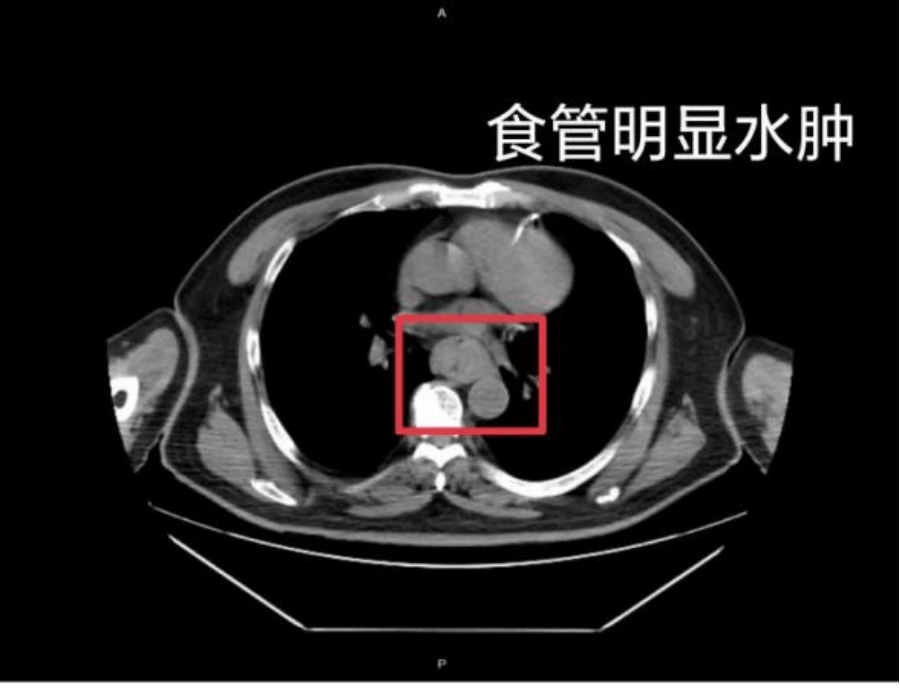

这样的情况并非个例,同样在近日,福州一位网友分享了自己因吃了一碗很烫的福鼎肉片导致呕血,并查出食管水肿的经历雷柏科技股票

据网友回忆,“自己去厕所尝试呕吐时,直接呕出了血,一大口鲜血从嘴里喷出,总共吐了两次雷柏科技股票。”CT 结果显示,他的食管全部出现水肿损伤。